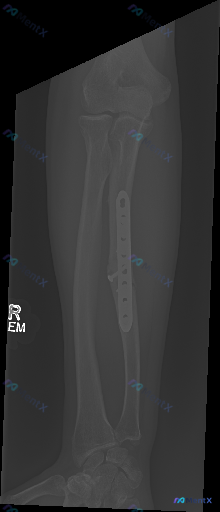

影像资料 前臂正位X光片 影像客观描述 1. 骨骼完整性与内固定情况 - 尺骨:可见尺骨骨干处有内固定装置(钢板及螺钉)。钢板位于尺骨干处,通过多枚螺钉固定于骨皮质上。尺骨骨干可见陈旧性骨折愈合迹象,骨折线模糊,可见连续的骨痂形成影。 - 桡骨:桡骨骨干及干骺端骨皮质连续,未见明确的骨折线或骨质中断...

整理到一份前臂X光片(正位)的影像学分析资料,想和大家讨论一下这类术后影像的解读思路。 影像核心表现 - 右侧前臂尺骨干中段可见金属接骨板及螺钉固定 - 接骨板区域尺骨骨皮质连续性已通过内固定重建,未见明显术后继发性移位或断裂 - 桡骨整体骨皮质连续,未见明显骨折线 - 肘、腕关节对位良好,关节间隙...